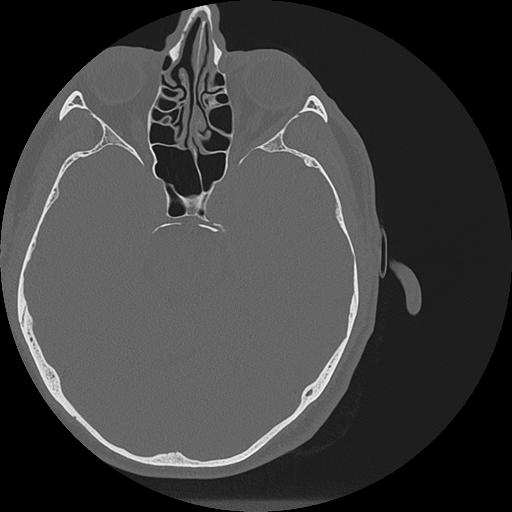

7 HUESO,,Vol,0.5,HUESO,,